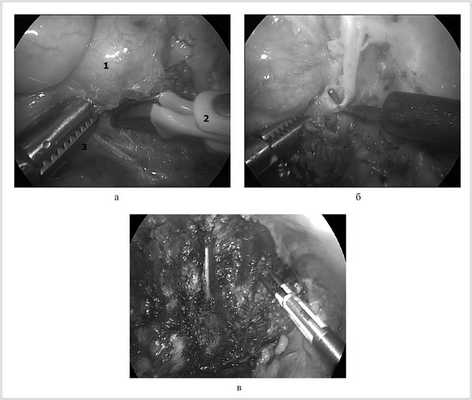

Перед началом удаления опухоли необходимо сориентироваться в топографии новообразования по отношению к крупным артериальным и венозным стволам: в первую очередь к подключичной артерии и вене, аорте, верхней полой вене; к диафрагмальному нерву, возвратному гортанному нерву, нервам плечевого сплетения и т. д. (рис. 2, а).

Рис. 2. Этапы операции.

Операцию начинают с выделения и пересечения симпатического ствола выше и ниже опухоли. Следующим этапом отсекают опухоль от задней грудной стенки. Особое внимание необходимо уделить гемостазу в межреберных промежутках. Опухоль может быть легко травмирована, поэтому лучше избежать непосредственного ее захвата инструментом, стараясь использовать для тракции медиастинальную плевру или отводя тупым путем без захвата собственно за ткань опухоли. При повреждении опухоли браншами зажима может отмечаться кровотечение. L-образный крючок использовали для выполнения тонкой диссекции объемного образования в бессосудистой зоне (см. рис. 2, б). Более зрелые опухоли имеют более плотную структуру и хорошо отделяются от окружающих тканей. Часто опухоль имеет плотные сращения с ребрами и прорастает в межпозвоночные отверстия, выходя в позвоночный канал. В такой ситуации целью операции не является полное удаление опухоли «en bloc». Основную часть опухоли удаляют, а оставшиеся фрагменты иссекают дополнительно или уничтожают путем аргоновой или электрокоагуляции (см. рис. 2, в). Удаленную опухоль погружают в эндомешок и удаляют через расширенное при необходимости отверстие 10-миллиметрового троакара. Ложе удаленной опухоли промывают, промывную жидкость полностью аспирируют. Гемостаз проверяют под эндоскопическим контролем. К ложу опухоли устанавливают плевральный дренаж. Легкое раздувают под визуальным контролем. Места вколов ушивают внутрикожным швом.